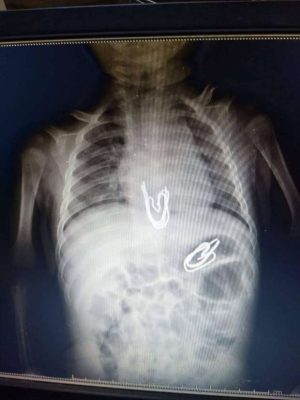

وكشف مدير عام مستشفى الأطفال الجامعي بالمنصورة، الدكتور أشرف الشرقاوي، عن تفاصيل الواقعة، موضحًا أنه جرى استقبال الطفل في وحدة الجهاز الهضمي والكبد بمستشفى الأطفال الجامعي بالمنصورة بقيادة الدكتور محمد عز، رئيس الوحدة، وبإجراء أشعة على البطن، تبين وجود مجموعة من المشابك المعدنية في المريء، وأخرى في المعدة، ولأن هذه المشابك ذات أطراف حادة فكان هناك تخوف من أن تكون جرحت جدار المعدة أو المريء، فتم عمل أشعة مقطعية أثبتت عدم وجود جروح.

وأكد رئيس وحدة الجهاز الهضمي والكبد بمستشفى الأطفال الجامعي بالمنصورة، الدكتور محمد عز، أن هذه الحالة تعد من الحالات الصعبة نظرا لعمر الطفل، ووجود عدد كبير من المشابك ذات الأطراف الحادة التي تحتاج لمهارة عالية في استخراجها.